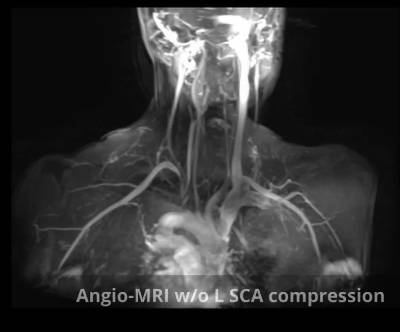

- AngioTAC Cervico- torácico/Angio RM cervico-torácica con maniobras de compresión